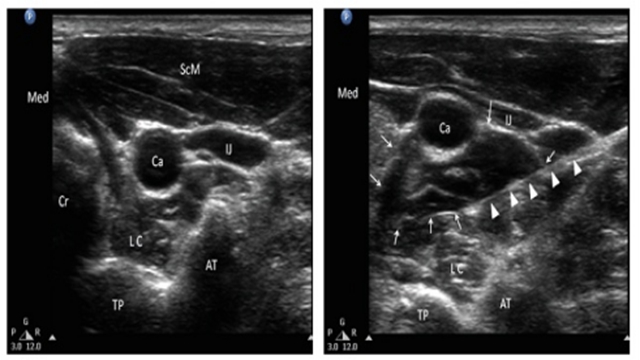

光靠中药还不够,刘庆教授还安排了“星状神经节阻滞”。即在彩超引导下,往脖子上的“星状神经节”打一点点药,相当于给神经“松绑”,能扩张头面部的血管,让王奶奶嘴唇和舌头的神经不再“缺血缺氧”;能调节自主神经,缓解王奶奶的心慌、胸口疼。